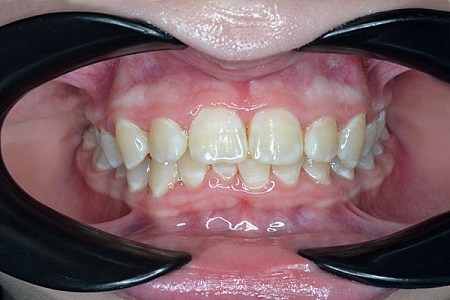

Работы наших врачей